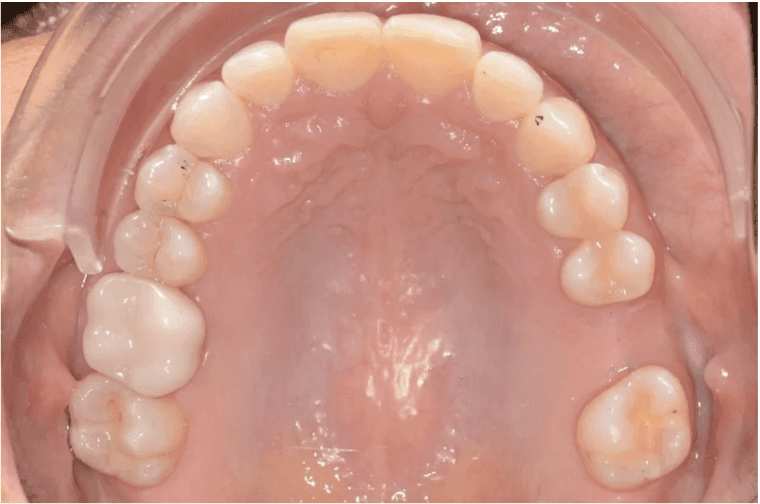

Diagnosis: Lower anterior crowding, LL3 crossbite, deep bite, missing UL6.

Final results

INTRAORAL